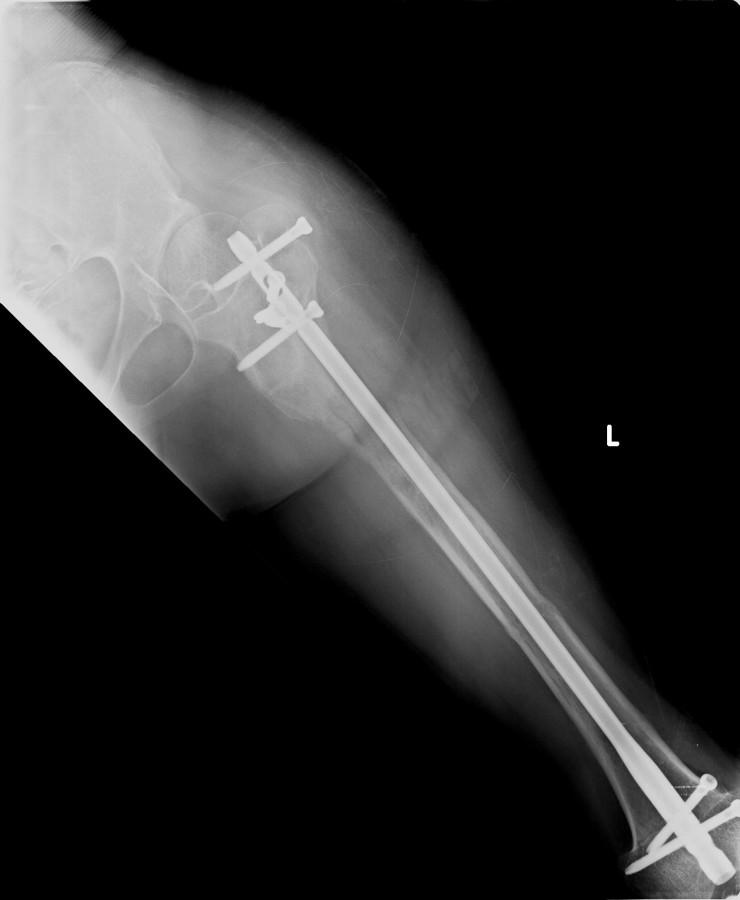

Vaka 2